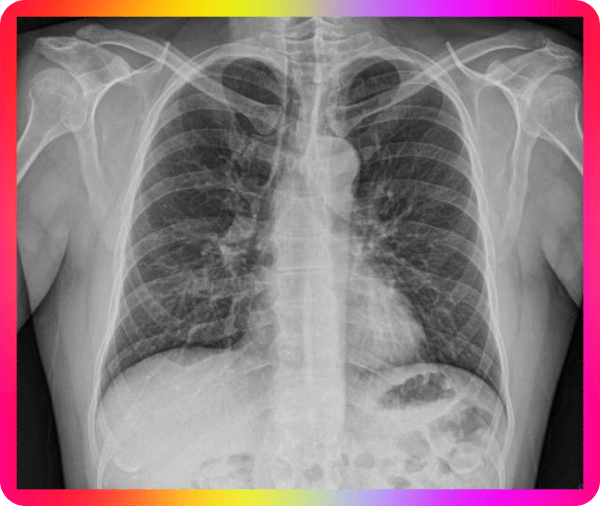

목 기관지와 폐에 가래가 생기면 답답한 가슴을 느낄 경우가 많은데, 너무 심하게 되면 가래를 제거를 해야 할 텐데요 청진기를 가슴에 대면 그르렁 거리를 소리를 듣게 될 텐데요 가래 생기는 이유와 가래 없애는 방법이 없을지 고민이 됩니다.

가래가 지속이 되는 경우 피가 섞여 나오게 되면 걱정이 되는데요 이런 경우 어떻게 해야 할지 난감해집니다. 가래 피가 섞여 나오면 혈담이라고 하고, 가래보다 혈액이 많으면 객혈이라고 하는데요 세균에 감염이 된 경우는 누렇거나 초록색에 가까워진다고 하는데요 반드시 흉부 CT촬영을 통해 검사를 받는 것이 좋다고 합니다.